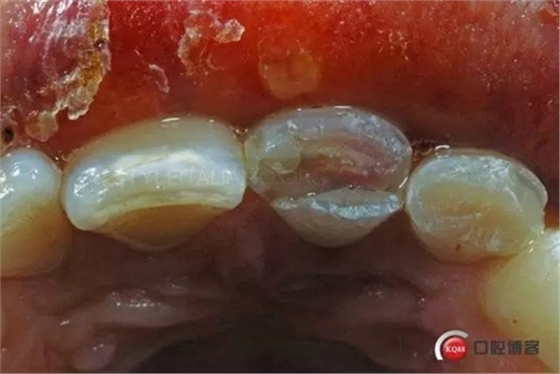

This is Italo, 32 years old, a few hours after a bicycle accident, coming from the hospital emergency room, on February 2006

The patient has a pulp hemorrhage on tooth 2.1 suffering for a deep palatal fracture